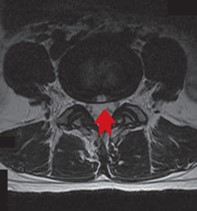

Die wichtigste Untersuchung ist die Kernspintomographie (MRT). Eine konventionelle Röntgenaufnahme, auf der die knöchernen Strukturen zu sehen sind und die mit einer lediglich geringen Strahlenbelastung verbunden ist, kann ergänzend weitere Informationen liefern.

Ein Vorfall kann rein in der Mittellinie des Spinalkanals auftreten aber auch seitlich oder er kann nach oben oder unten abrutschen. Man spricht von medialen, mediolateralen, lateralen, foraminalen, cranialen und caudalen Vorfällen / Sequestern. Diese Einteilung ist für die auftretende Symptomatik aber auch für die ggf erforderliche OP Planung sehr wichtig.